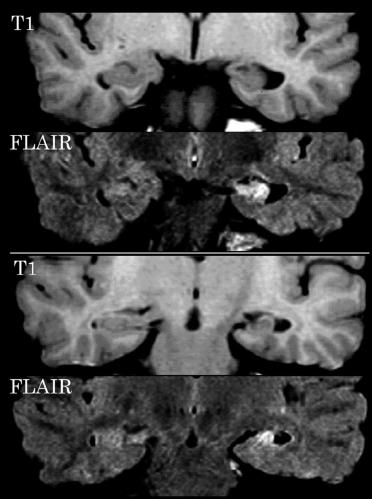

图 癫痫的影像学检查